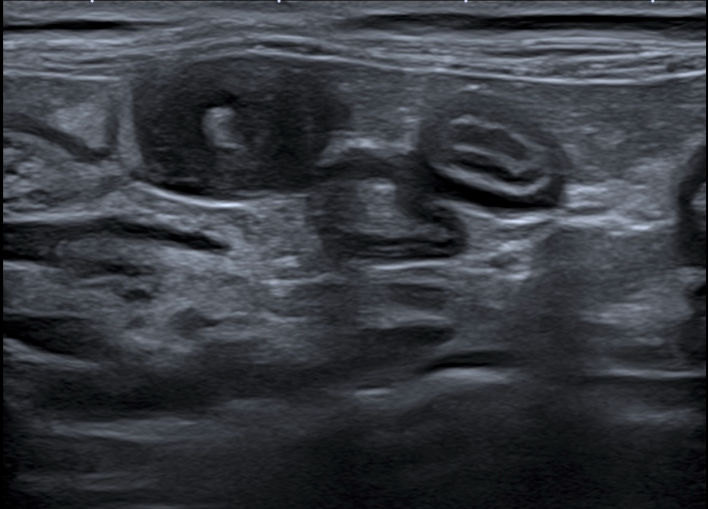

Jour 1 : Le système digestif, vaisseaux et nœuds lymphatiques tributaires.

• Rappeler l’écho anatomie du tube digestif, des vaisseaux et des nœuds lymphatiques tributaires

• Savoir décrire les images anormales du tube digestif, des vaisseaux et des nœuds lymphatiques tributaires

• TP d’échographie sur chats

• Interpréter exercices dirigés de reconnaissance et description d’images normales et anormales du tube digestif, des vaisseaux et des nœuds lymphatiques tributaires.

• TP d’échographie sur chats.